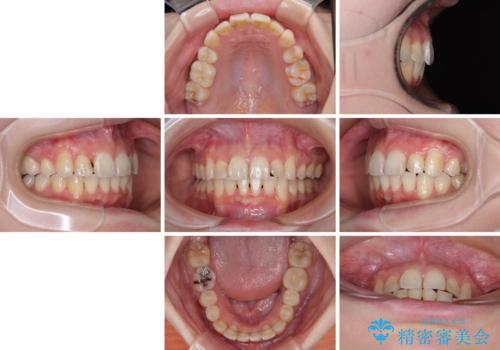

- 前歯のデコボコを気にして来院された患者様です。

上下の前歯にデコボコがあり、更にはディープバイトにより下顎前歯の大半が隠れている状態でした。

上顎左右第一小臼歯の2本を抜歯し、ワイヤー装置を使用して咬み合わせ高さを改善しながら、歯列を整えて行くこととしました。

事前にむし歯の疑いがある歯があり、処置を行いましたが、矯正治療中に失活してしまい、ワイヤー装置除去後に、根管治療とセラミッククラウンによる補綴治療を行いました。

矯正治療は2年半ほで無事におけることができました。